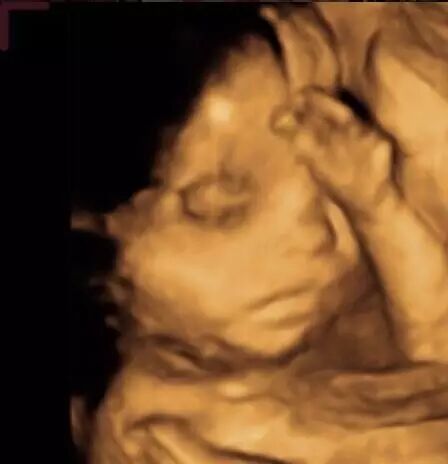

▲即将出生的小女儿

你陪妈妈产检,拍了无数妹妹的照片,一直喊好感动。